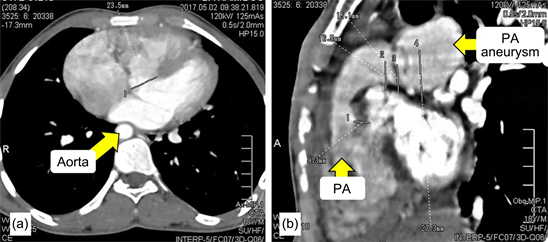

Surgery was indicated and was done for this patient. After a median sternotomy, intraoperative exploration, under cardiopulmonary bypass with bicaval cannulation and moderate hypothermia, showed dilatation of the right heart chambers which was thick. The pulmonary artery trunk and its branches were dilated without major aneurysm. The absence of pulmonary valve was noted (Figure 2). A significant infundibular stenosis and a sub-aortic 14 mm wide large ventricular septal defect were founded.

Figure 2. Operative view showing the absence of pulmonary valves (Arrow).